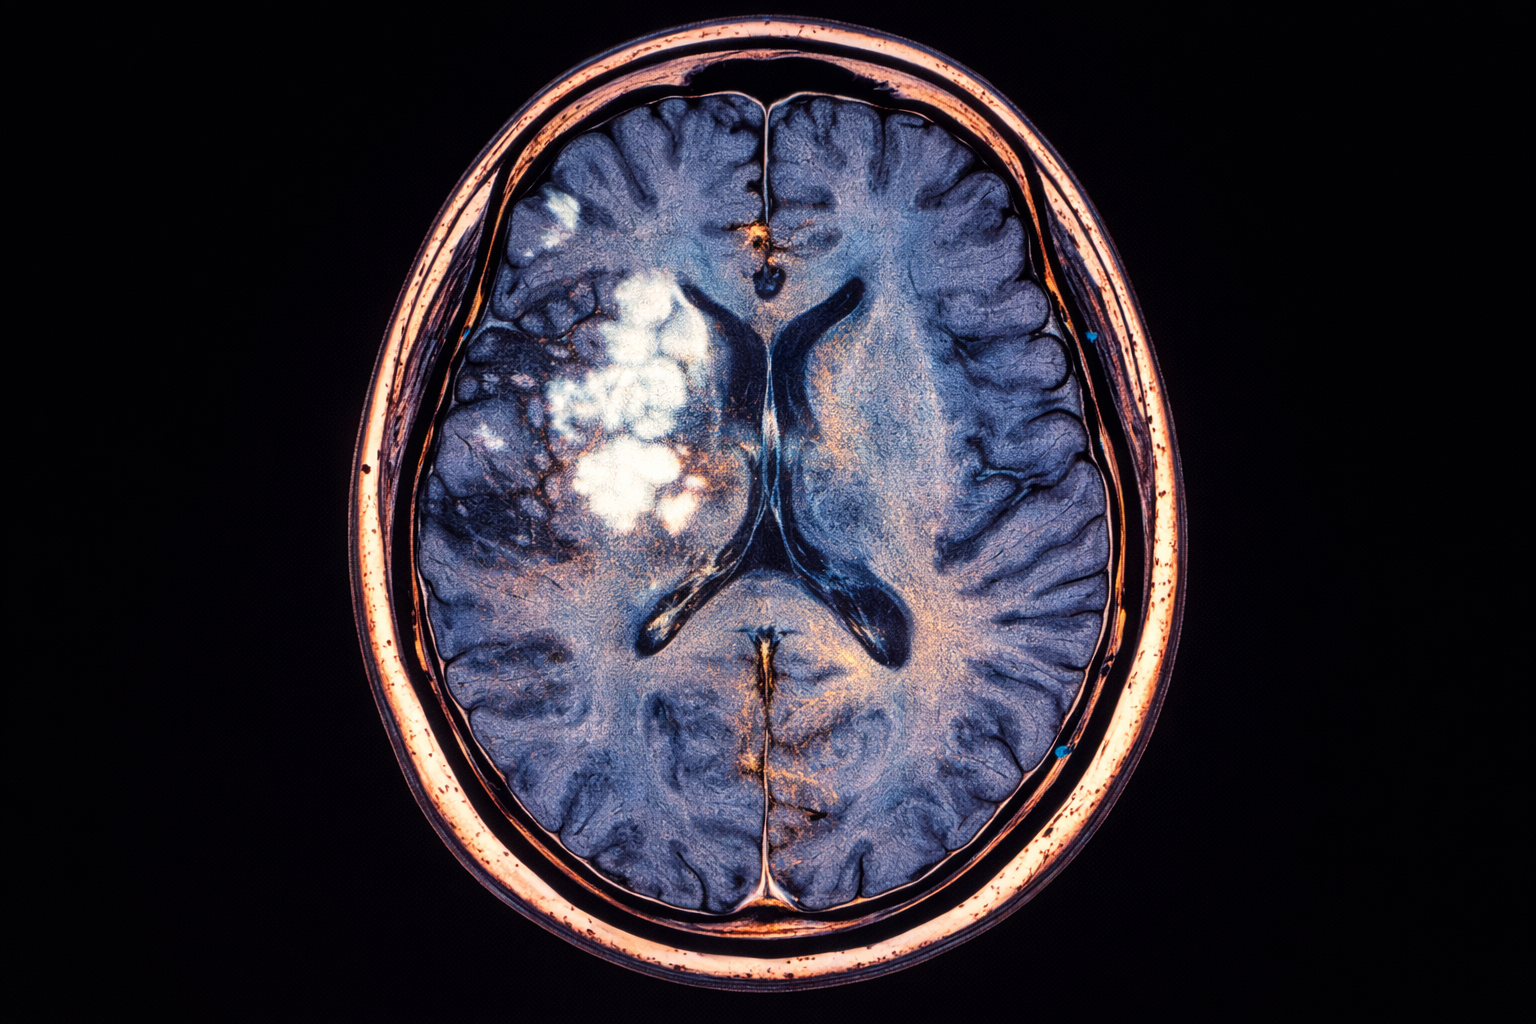

MRI glave sa kontrastom je napredna dijagnostička metoda koja omogućava još precizniji prikaz moždanih struktura i krvnih sudova uz primjenu kontrastnog sredstva. Ova metoda se koristi kada je potrebno detaljnije analizirati sumnjive promjene koje se ne mogu jasno razlikovati na standardnom MRI pregledu. Kontrast omogućava bolju vidljivost tumora, upalnih procesa i vaskularnih promjena. Pregled je siguran, bezbolan i ne koristi ionizirajuće zračenje, što ga čini pouzdanim izborom u savremenoj dijagnostici.